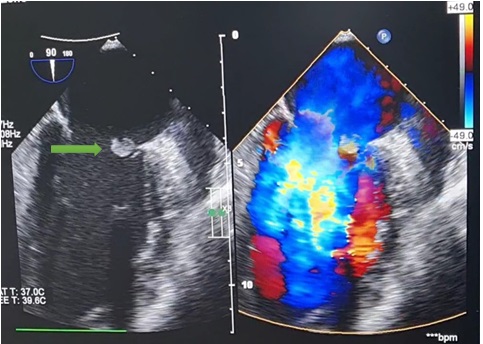

Siêu âm tim anh T phát hiện cục sùi lớn (mũi tên xanh), gây thủng van và làm hở nặng van hai lá.